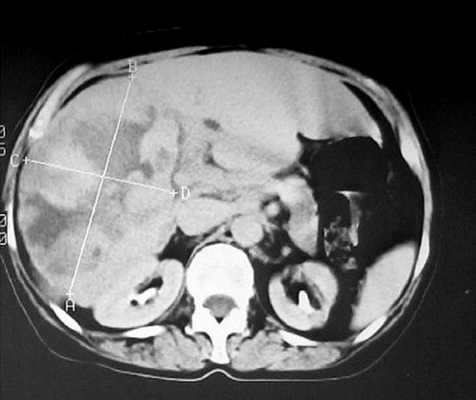

В нашем случае при ультразвуковом исследовании брюшной полости выявлено атипичное строение гемангиомы, динамическая компьютерная томография указывает на типичную гемангиому (рис. 2а, б). При этом важно знать, что только приблизительно в 54% случаев у больных с гемангиомами имеет место характерная перфузия с центростремительным усилением и поздним заполнением [20]. Однако в связи с тем, что этот тип усиления встречается только у 1,6% первичных и вторичных злокачественных опухолей печени, определение структуры данного усиления позволяет уверенно дифференцировать гемангиомы от злокачественных печеночных опухолей [20].

Рис. 2. КТ печени.

а) До контрастирования - в левой доле печени видно большое образование округлой формы.

КТ брюшной полости. Печень увеличена в размерах, неоднородная по эхоструктуре, признаков портальной и билиарной гипертензии нет. В правой доле печени, занимая практически всю долю, определяется дополнительное объемное образование, неоднородно пониженной плотности, с неровными четкими контурами, размером 143х93 мм. После введения контрастного вещества образование неравномерно накапливает его от периферии к центру, в виде языков пламени. В центре образования определяется участок равномерно низкой плотности, продолговато-ветвистой формы, с четкими контурами (гиалиновая щель). В центре образования видны участки кальцификации. В отсроченной фазе образование продолжает неравномерно накапливать контрастное вещество, максимальное его накопление отмечено в центре. Поджелудочная железа без особенностей. Селезенка нормального размера, структурно не изменена.

Заключение: гигантская кавернозная гемангиома правой доли печени (рис. 2).

а) Паренхиматозная фаза.

б) Паренхиматозная фаза.

в) Отсроченная фаза.